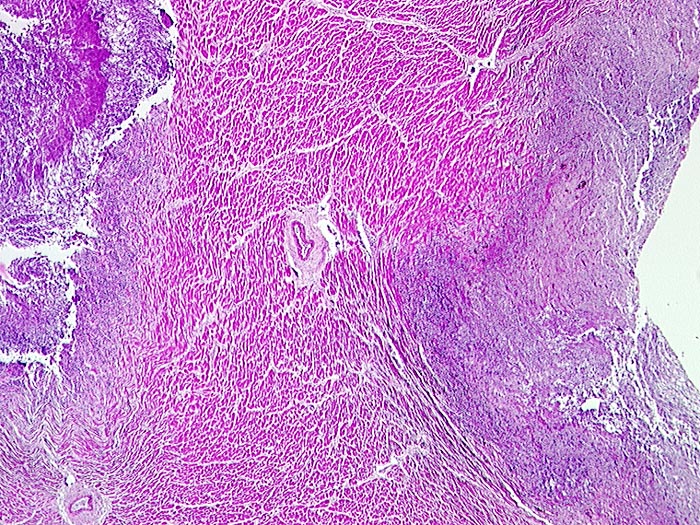

Septisch embolische Myokarditis: Aspergillussepsis

Entzündung infektiös

Herz links

Ausgedehnte Myokardnekrosen (blaue Areale)

Septische Herde in Haut, Nieren und Herz

Chronische lymphatische Leukämie. St.n. Chemotherapie. Steroiddauertherapie.